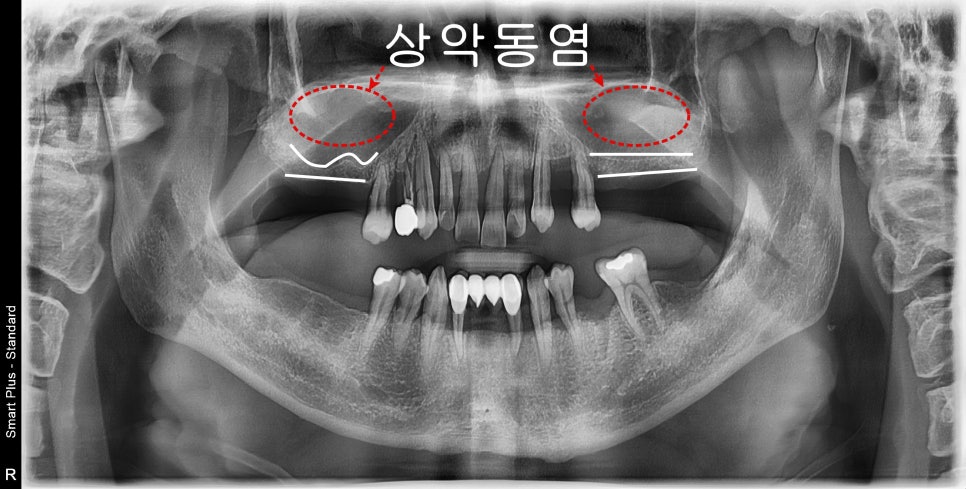

희색선=남아있는 치조골, 빨간원=상악동공간

어금니가 장기간 동안 상실된 상태이셨고

앞니 쪽으로 식사를 주로 하시다 보니

치주가 안 좋은 곳은 동요도가 심한 상태였습니다.

진단을 하기 전에 상악동 공간에 뿌옇게

염증소견이 보였습니다.

CT상에서 회색으로 보이는 공간은

만성비염에 의해 점막의 비후는 물론이고

염증이 차 있는 것을 볼 수 있습니다.

저 해당 공간은 상악동거상술을 통한

치조골 이식술을 해야 하는 공간입니다.

현재 상태에서는 적절하게 점막을 거상할 수 없기 때문에

이비인후과와 협진을 통해 비염수술을 완료 한 후에

위턱뼈의 임플란트 수술을 진행하기로 했습니다.